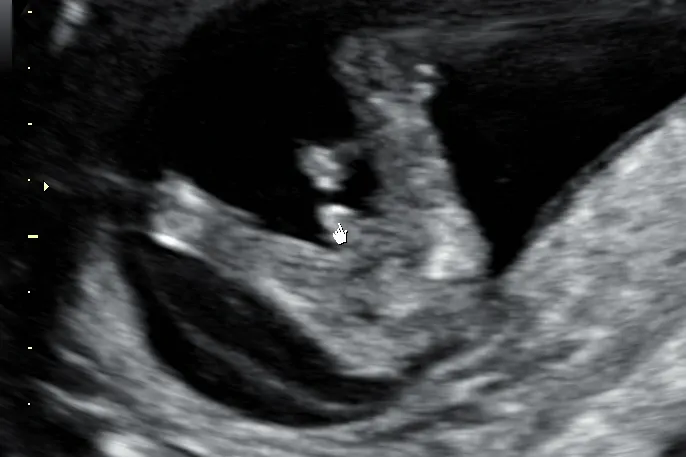

Badanie ultrasonograficzne (USG) to podstawowe narzędzie diagnostyczne w ciąży, które pozwala nam wizualnie ocenić rozwój płodu. W kontekście określania płci, podczas USG poszukujemy konkretnych struktur anatomicznych. U chłopców jest to widoczne prącie i moszna, natomiast u dziewczynek wargi sromowe. Jednak nie zawsze jest to takie proste, jak mogłoby się wydawać.

W okolicach 14-16 tygodnia ciąży, podczas tak zwanego USG genetycznego, doświadczony lekarz może podjąć próbę oceny płci. Muszę jednak podkreślić, że na tym etapie wiarygodność jest jeszcze niższa. Głównym celem tego badania jest przede wszystkim ocena prawidłowego rozwoju płodu i wykluczenie ewentualnych wad genetycznych, a informacja o płci jest raczej dodatkiem, który może, ale nie musi być w pełni pewny.

Prawdziwym "złotym standardem" w określaniu płci dziecka za pomocą USG jest badanie połówkowe, wykonywane zazwyczaj między 18. a 22. tygodniem ciąży. Na tym etapie narządy płciowe są już znacznie lepiej rozwinięte i widoczne, co pozwala na określenie płci z bardzo wysoką skutecznością, przekraczającą 95-98%. To właśnie wtedy większość rodziców dowiaduje się, czy spodziewa się chłopca, czy dziewczynki.